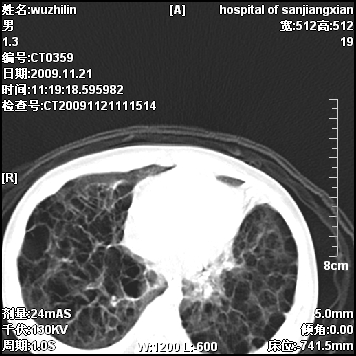

弥漫性薄壁囊腔,胸膜下及肺底部占优势,双上肺磨玻璃密度影,首先考虑特发性肺间质纤维化,其次囊性肺纤维化,肺淋巴管平滑肌瘤病嗜酸性肉芽肿等;要结合临床综合考虑。

两肺布满多个薄壁含气囊腔,以下肺居多,伴磨玻璃样密度影,左侧气胸。两肺发育不全、两肺多发肺囊肿并感染,其次考虑肺囊腺瘤。